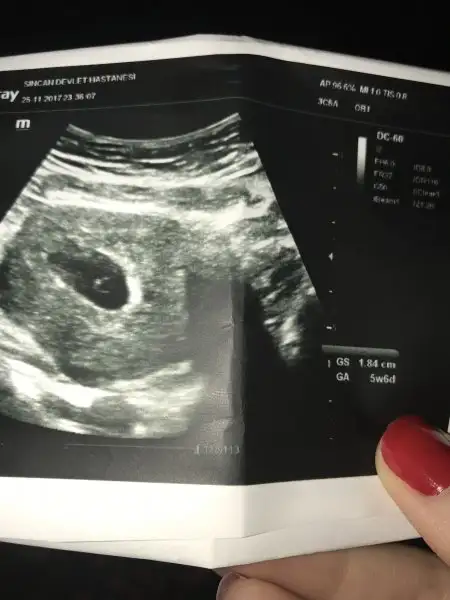

Kızlar ultrasonum da bu şekildeydi . Maşallah minik mercimeğim sağlıklı imiş .. Şimdi sadece dinlenip ilaçlarımı kullanıyorum . Yine kahve lekelenmem devam ediyor tam olarak geçmiş değil . Bu görüntü de ayın 25ine ait . Sizinle de paylaşmak istedim

• image.webp

14,9 KB · Görüntüleme: 74